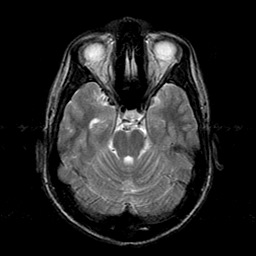

Sarcoma, MR Study #1 mr-t2 -- Slice #7

[Home][Help][Clinical] Slice 7